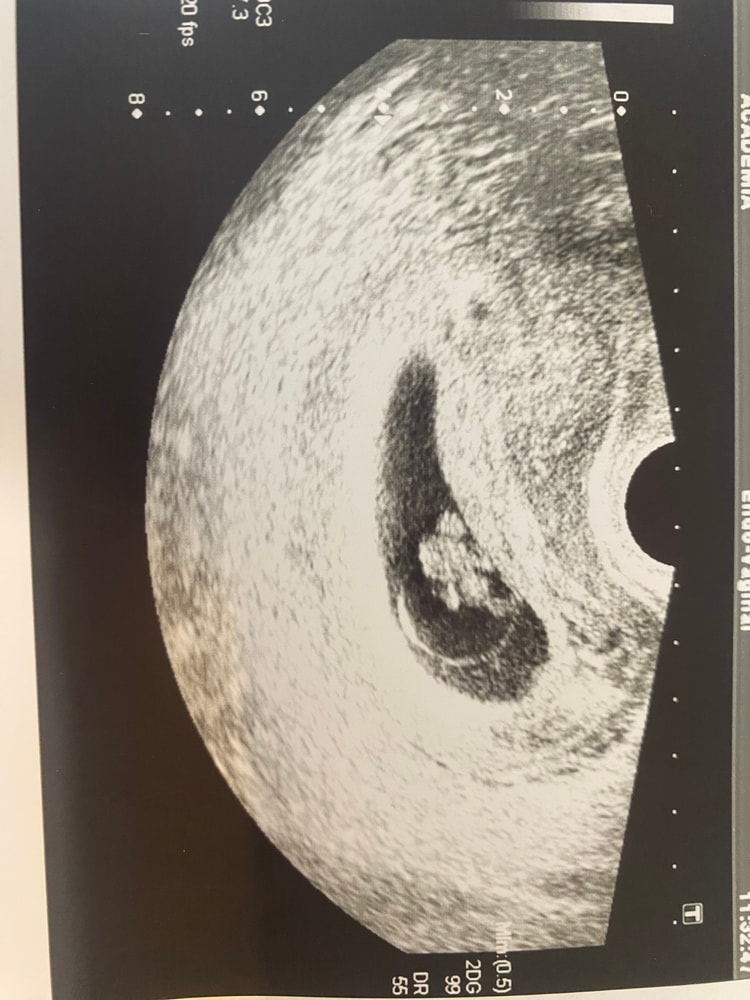

Деля , верхнее 7 недель, нижнее сегодня 8,4 Изображение Изображение

Екатерина , ну по снимку очевидно, что вырос хорошо) Измерили неправильно